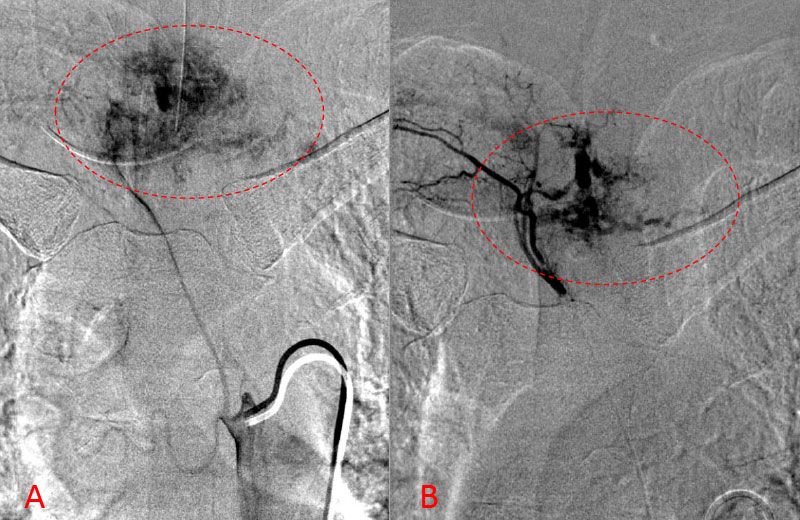

No spinal artery contributions were found to arise from this right T1-T3 pedicle. Superselective WADA testing was performed with Brevital injected through the microcatheter, which failed to elicit changes in the intraoperative monitoring, confirming safety to proceed with devascularization of this pedicle and tumor. This was performed with 100-300 micron particles achieving an excellent devascularization (Figure 3. A, B).

Figure 3. A and B) demonstrates selective PVA embolization with complete devascularization of the tumor on completed embolization

The patient underwent a safe and successful posterior decompression with corpectomy and instrumented fusion with minimal blood loss and discharged home with reversal of neurologic deficits and resolution of symptoms.